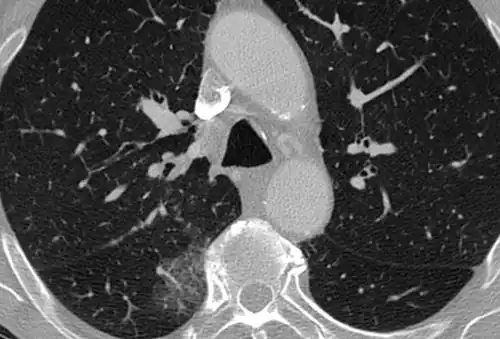

Ground-glass opacity (GGO) is a finding seen on chest x-ray (radiograph) or computed tomography (CT) imaging of the lungs. It is typically defined as an area of hazy opacification (x-ray) or increased attenuation (CT) due to air displacement by fluid, airway collapse, fibrosis, or a neoplastic process.[1] When a substance other than air fills an area of the lung it increases that area's density. On both x-ray and CT, this appears more grey or hazy as opposed to the normally dark-appearing lungs. Although it can sometimes be seen in normal lungs, common pathologic causes include infections, interstitial lung disease, and pulmonary edema.[2][3]

Ground-glass opacity is most often used to describe findings in high-resolution CT imaging of the thorax, although it is also used when describing chest radiographs. In CT, the term refers to one or multiple areas of increased attenuation (density) without concealment of the pulmonary vasculature. This appears more grey, as opposed to the normally dark-appearing (air-filled) lung on CT imaging. In chest radiographs, the term refers to one or multiple areas in which the normally darker-appearing (air-filled) lung appears more opaque, hazy, or cloudy. Ground-glass opacity is in contrast to consolidation, in which the pulmonary vascular markings are obscured.[3][5] GGO can be used to describe both focal and diffuse areas of increased density.[5] Subtypes of GGOs include diffuse, nodular, centrilobular, mosaic, crazy paving, halo sign, and reversed halo sign.[6]